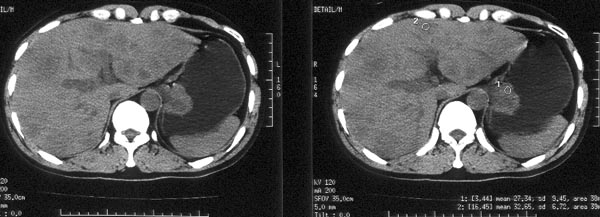

男性,46岁。腹痛月余。胃镜检查示“胃贲门区占位”,活检病理示

“胃贲门癌”。

ct平扫:胃贲门部见软组织肿物突入胃腔内,大小4x3cm,浅分叶状,中央密度较低,邻近胃壁增厚。外缘与周围组织分界清。im25层面,小网膜囊区见两枚肿大淋巴结,直径均约3cm。肝脏大小正常,肝内散在分布多个大小不等的类圆形低密度影,最大者位于肝右前叶上段,直径约4cm,病灶边缘模糊,与正常肝实质分界欠清。

ct诊断:胃贲门癌,并腹腔淋巴结转移及肝内多发转移。